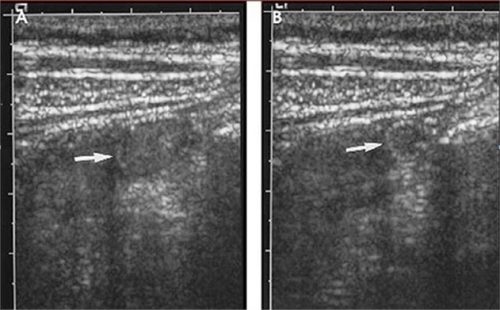

Hình ảnh ruột thừa bình thường

Ruột thừa bình thường

Hình A. Ở vùng hố chậu phải, hình ảnh 1 vòng chứa đầy dịch đường kính

Hình B. Khi nén đường kính ruột thừa giảm còn